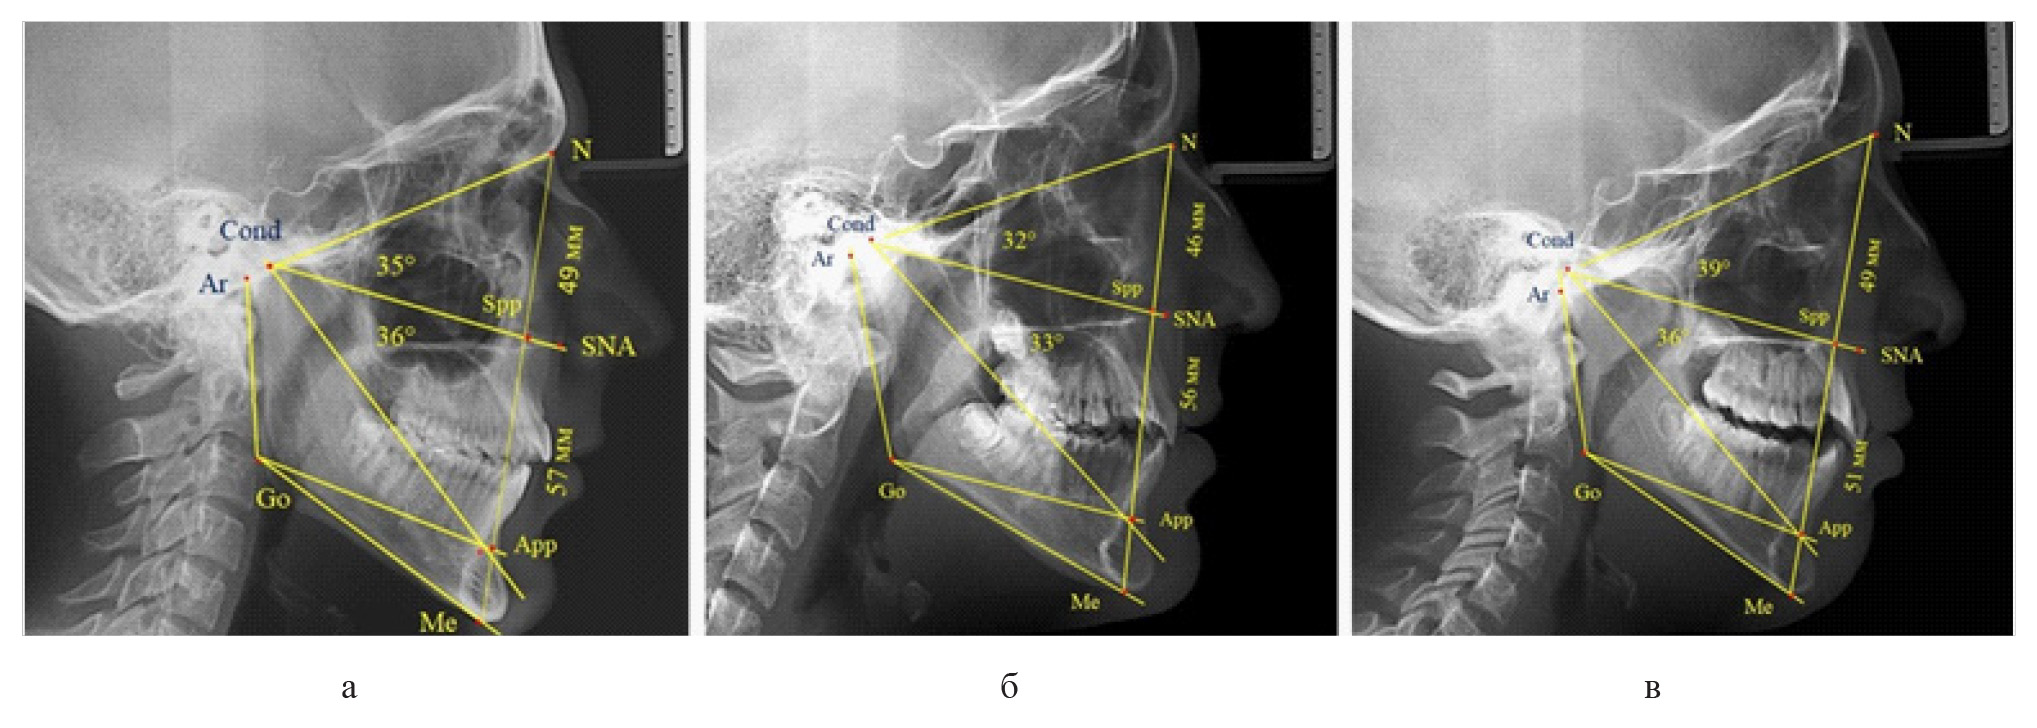

Полученные данные позволили разработать рабочую схему для определения физиологических и патологических вариантов роста лица (рис. 2).

Рис. 2. Рабочая схема дифференциальной диагностики физиологических и патологических вариантов роста лица

У 6 человек [(10,71 ± 4,13) %], отмечалось увеличение параметров гнатической части до уровня физиологического вертикального показателя, а у 2 человек [(3,57 ± 2,48) %], незначительное снижение гнатической части (рис. 3).

Рис. 3. Сравнительный анализ ТРГ с оптимальными размерами носового отдела и оптимальными (а), укороченными физиологическими (б) и увеличенными физиологическими (в) размерами гнатической части лица